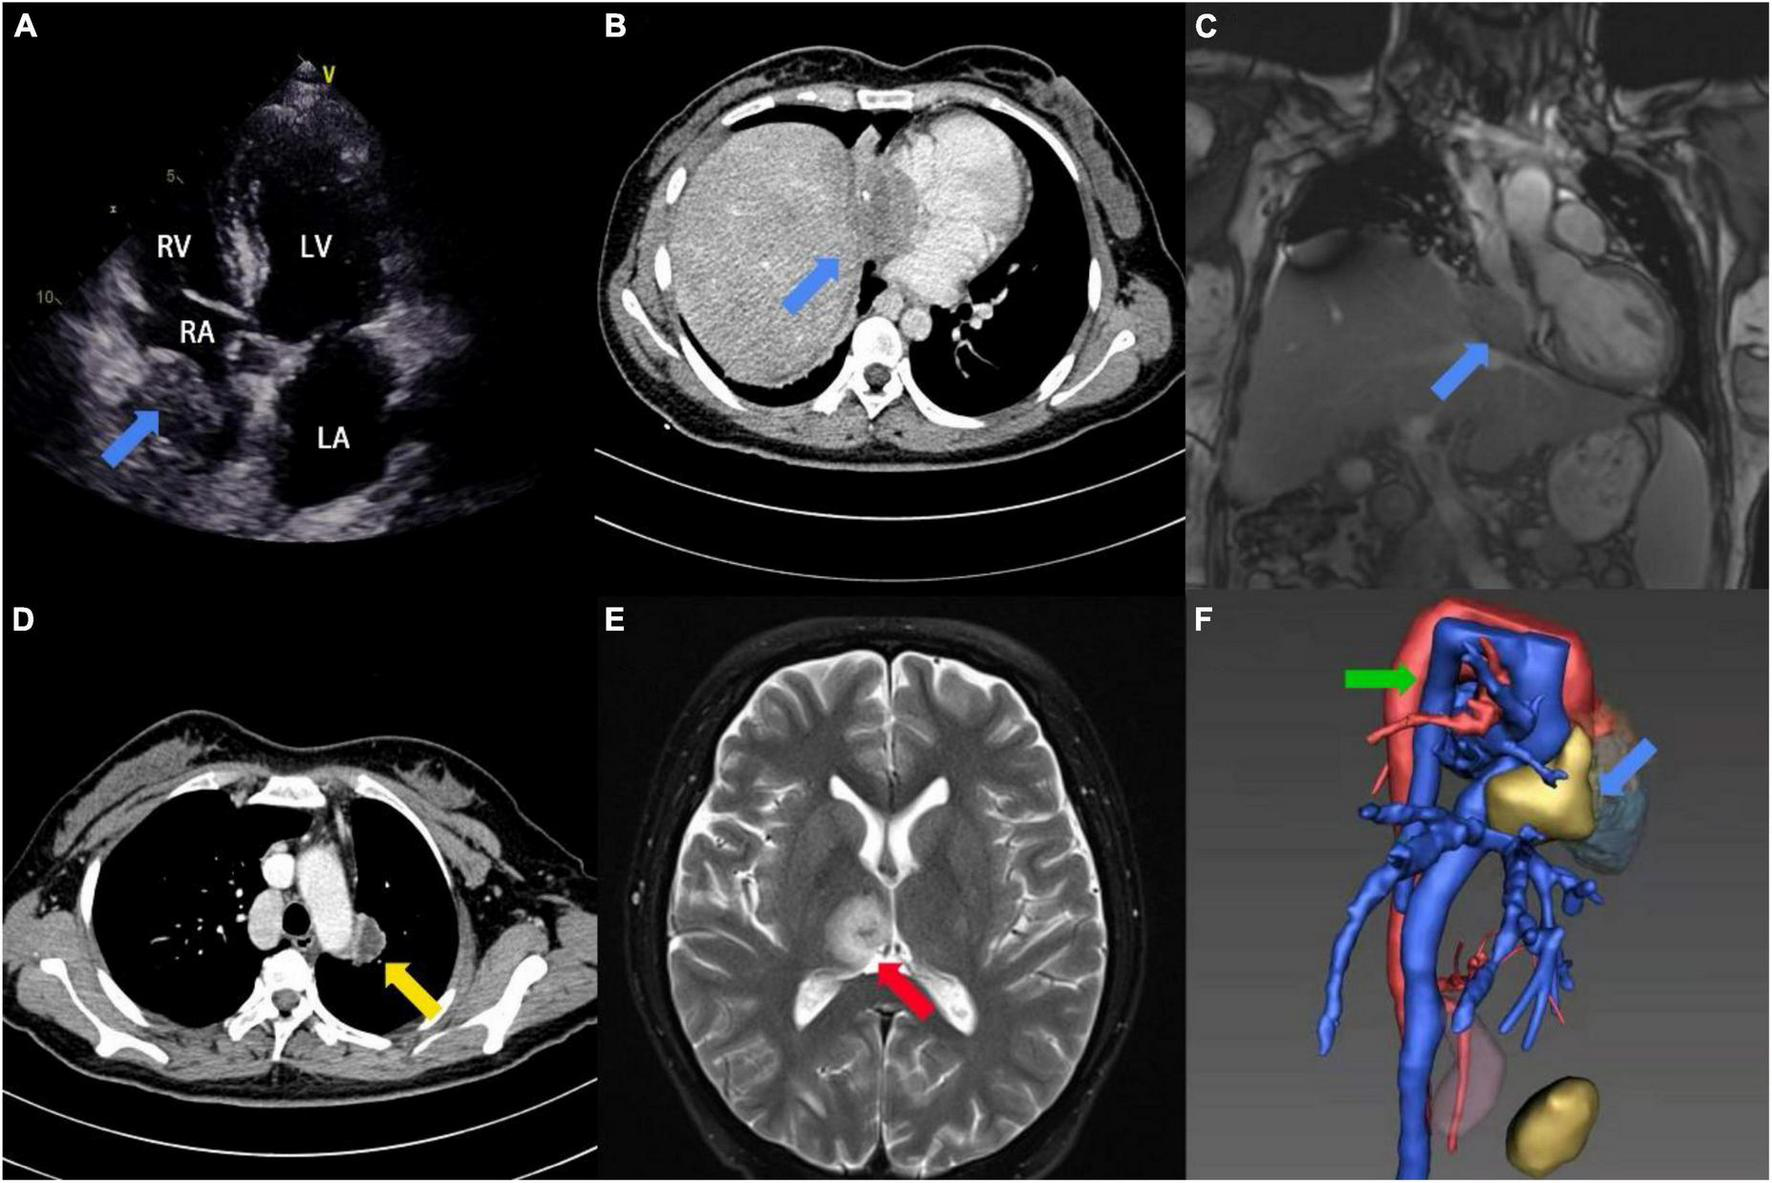

A 31-year-old female patient was admitted to the hospital with repeated hemoptysis and dyspnea on exertion for 3 years. In addition, a fever reaching 39°C and watery diarrhea had occurred 4 days before admission. Long-term residence history in an endemic area of echinococcosis was confirmed on admission. On physical examination, the patient presented with persistent tachycardia of 102 beats per minute. Besides, the cardiac murmur was not found during auscultation of the heart. Peripheral blood test demonstrated concurrent moderate anemia with the hemoglobin (Hb) of 85 g/L and eosinophilia with the eosinophil percentage (EO%) of 10.6%. The hepatic function test showed elevation in total bilirubin (TBIL, 32.1 μmol/L) and direct bilirubin (DBIL, 16.4 μmol/L), while alanine transaminase (ALT) and aspartate transaminase (AST) remained normal. Furthermore, detection of the echinococcosis granulosus IgG was positive. Preoperative transthoracic echocardiography (TTE) revealed a 24 mm × 50 mm immobile mass extending from the inferior vena cava (IVC) into the right atrium. There was no clear boundary between the epicardium and the mass (Figure 1A). Computed tomography angiogram (CTA) and magnetic resonance imaging (MRI) confirmed the mass, while multiple lesions were also found in the left lung and the brain (Figures 1B–E and Supplementary Video 1). In addition, the azygos vein dilated significantly as a compensatory sign of IVC obstruction (Figure 1F). Transbronchoscopic lung biopsy demonstrated that the pathological diagnosis of the left lung lesion was granulomatous inflammation resulting from echinococcosis infection.

FIGURE 1

Image findings. (A) Preoperative 2D-TTE four-chamber view showed an irregular mass (blue arrow) within the right atrium. (B) Preoperative CTA showed a mass with slight calcification (blue arrow) within the right atrium and IVC. (C) Preoperative MRI showed a hypointense mass (blue arrow) at the junction of the right atrium and IVC on coronary-reconstruction view. (D) Preoperative CTA showed a lesion with slight enhancement in the left lung (yellow arrow). (E) Preoperative MRI showed an oval hypertense lesion (red arrow) within the brain on T2-weighted image. (F) 3D-reconstruction view of preoperative CTA showed the cardiac mass (blue arrow) and enlarged azygos vein (green arrow).